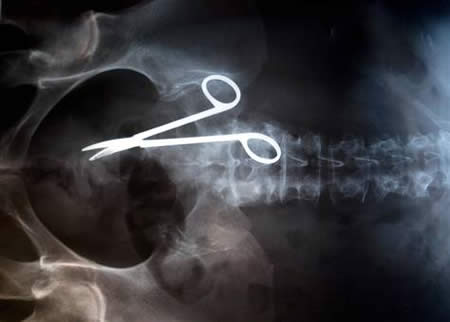

After a car accident and a long wait in the E.R., the doctors may do some kind of imaging study like an x-ray or MRI. Unless you have a broken bone, punctured lung, internal bleeding or some other life threatening injury, ... Fetch Doc